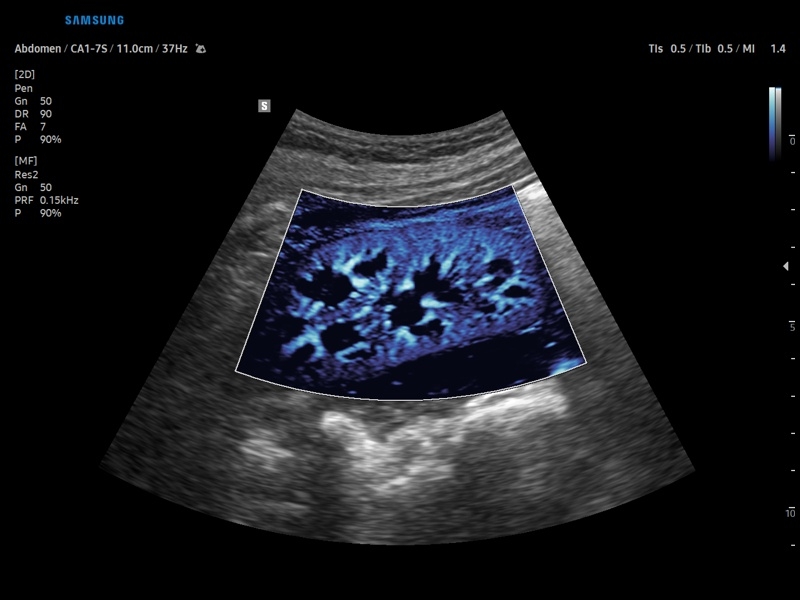

• Контрастное усиление CEUS+

• Модуль CEUS+ (Contrast Enchansment UltraSound) - программа, позволяющая проводить обследование с применением контрастных агентов.

• Модуль MV-Flow – программа (режим), позволяющая визуализировать кровоток в микроциркуляторном русле с высоким разрешением без использования контраста.

• Модуль LumiFlow – программа отображения кровотока с объемной графикой для лучшего понимания архитектоники сосудистого русла.

• Программа SEE Stream – режим недопплеровской визуализации кровотока в реальном масштабе времени.

• Абдоминальные исследования